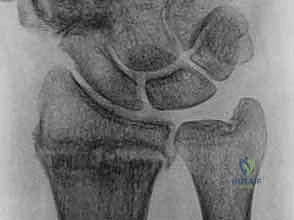

رأس الزند يشكل نقطة الارتكاز التي تستند عليها اليد والكعبرة

الكعبرة تدور حول رأس الزند عبر المفصل الزندي الكعبري البعيد

المفصل الزندي الكعبري البعيد مستقر بفضل التوافق العظمي والأربطة

2. كسور رأس الزند (Ulnar Head Fractures)

رأس الزند هو الجزء المفصلي الدائري الذي يدور حوله الكعبرة.

* كسور مفصلية (Articular Fractures): تمتد خطوط الكسر لتشمل الغضروف المفصلي. إذا لم يتم إعادة العظام إلى وضعها التشريحي المثالي (Anatomic Reduction)، فإن المريض سيكون عرضة للإصابة بخشونة المفاصل المبكرة (Post-traumatic Osteoarthritis) وفقدان القدرة على تدوير الساعد.

* كسور غير مفصلية: تقع تحت السطح المفصلي مباشرة، ولكنها قد تؤدي إلى تشوه في زاوية رأس الزند.

صورة لكسر في رأس الزند